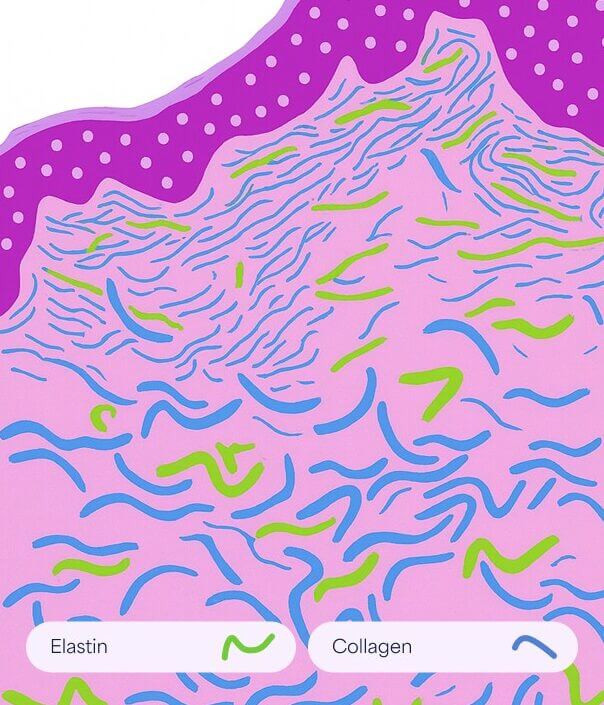

Normal Skin

Smooth and elastic with intact collagen and elastin fibers maintaining firmness and structure.

Striae Rubrae

Smooth and elastic with intact collagen and elastin fibers maintaining firmness and structure.

Striae Albae

Mature white stretch marks where collagen remodeling leads to thinning and loss of pigmentation.

How it works

- Promotes removal of damaged collagen

- Induces keratinocytes proliferation that releases growth factors to promote collagen deposition by the fibroblasts and elastin deposition

- Modulates the expression of several genes in the skin (vascular endothelial growth factor, fibroblast growth factor, epidermal growth factor, collagen type I and III) that promote extracellular matrix remodeling